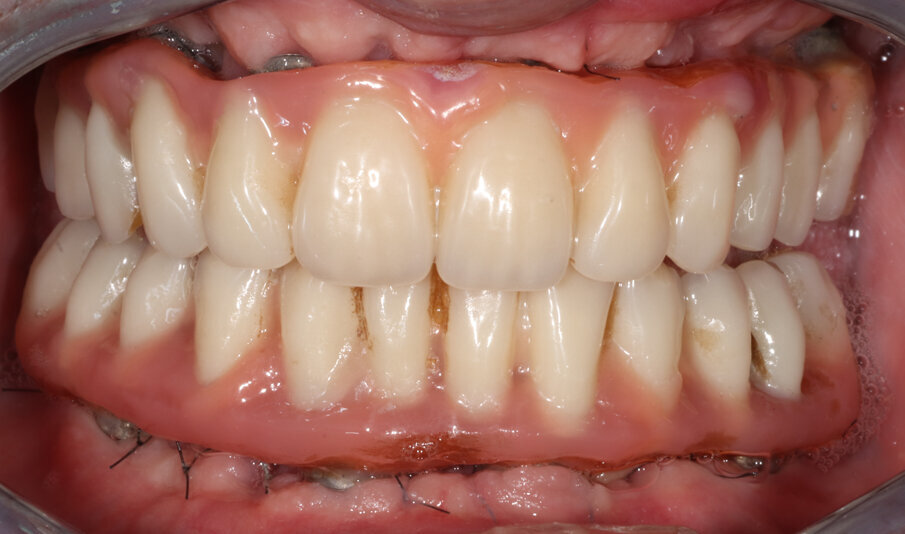

Il paziente è stato dimesso con la prescrizione di Amoxicillina (875 mg) e Acido Clavulanico (125 mg) tre volte al giorno, per sei giorni, Ibuprofene 600 mg al bisogno e sciacqui con Clorexidina 0,12% 3 volte al giorno, per 21 giorni, a cominciare dal giorno successivo l’intervento. Il decorso post-operatorio è stato privo di complicanze e i controlli sono stati programmati con cadenza bisettimanale per due mesi. Trascorsi i due mesi le protesi provvisorie sono state svitate e gli impianti sono stati verificati singolarmente. Non sono stati rilevati segni di infiammazione o infezione, né mobilità implantare (Fig. 8).

Fig. 8_Situazione clinica dei tessuti molli a distanza di due mesi dall’inserimento degli impianti.